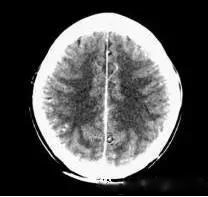

(機器故障偽影:常為環(huán)形或同心圓狀高密度偽影)

2、機器故障偽影的形狀機器故障所至偽影的形狀各種各樣,有非同心圓形和同心圓形(單同心圓和多同心圓、直線形、柵格形條紋狀)、星狀,還有不規(guī)則形,一般來說.根據(jù)偽影形狀可大致區(qū)分為機器哪一個系統(tǒng)故障所致。

如:單同心圓可能為通道板故障、連續(xù)屏蔽多個通道,多同心圓可能為環(huán)境溫濕度變化較大,AD控制板故障、線性電源問題、高壓線性電源問,滿屏斜條或直線可能為高壓系統(tǒng)故障·不規(guī)則形則可能為球管老化所致。